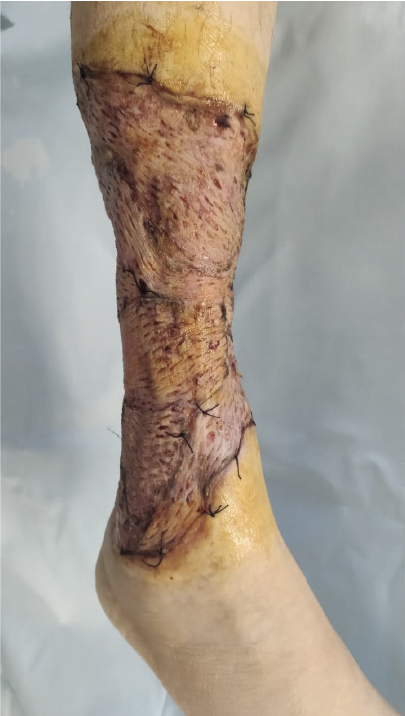

К 16 ноября 2021 г. удалось очистить рану от наложений фибрина, ликвидировать «гнойные карманы», подготовить грануляции к оперативному восстановлению кожного покрова и выполнить аутодермопластику расщепленными перфорированными трансплантатами на площади 1,5% поверхности тела (рис. 4). Терапия на момент трансплантации: метилпреднизолон 40 мг/сут, метронидазол 1000 мг/сут, месалазин 4 г/сут, омепразол 40 мг/сут.

Рис. 4. Состояние после аутодермопластики расщепленными перфорированными трансплантатами (21 ноября 2021 г.)

С ноября 2021 по октябрь 2022 г. (пациентка прослежена на эту дату) проведен полный индукционный курс инфликсимаба с переходом на поддерживающее лечение в режиме 300 мг каждые 8 недель, системные глюкокортикостероиды (ГКС) полностью отменены. На фоне проводимого лечения сохраняется клиническая ремиссия БК, купированы анемия и латентный железодефицит, отмечена нормализация количества тромбоцитов, уровня белков крови и С-реактивного белка. Контрольное исследование эндоскопической активности БК откладывалось по семейным обстоятельствам пациентки. На правой голени (рис. 5) – оперативно восстановленный рубцово-измененный кожный покров, плотно спаянный с подлежащими тканями, не ограничивающий движения, без признаков мацерации, изъязвления и гипертрофического роста.

Рис. 5. Вид конечности 25 января 2022 г. (спустя 2 месяца после аутодермопластики)